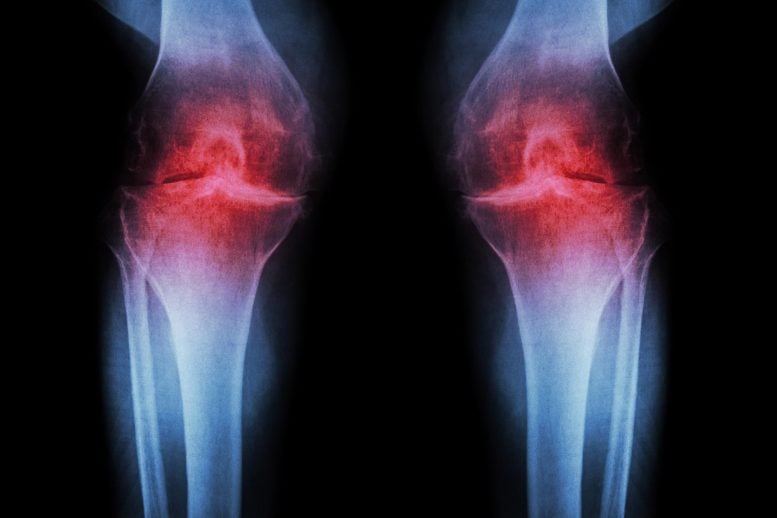

A treatment that blocks an age-related protein restored cartilage in aging and injured joints by reprogramming existing cells rather than using stem cells. Researchers at Stanford Medicine report that blocking a protein linked to aging can restore cartilage that naturally wears away in the knees of older mice. In the study, the injectable treatment not […]Health,Arthritis,Regenerative Medicine,Stanford University,Stem Cells#AntiAging #Injection #Regrows #Knee #Cartilage #Prevents #Arthritis1767445977